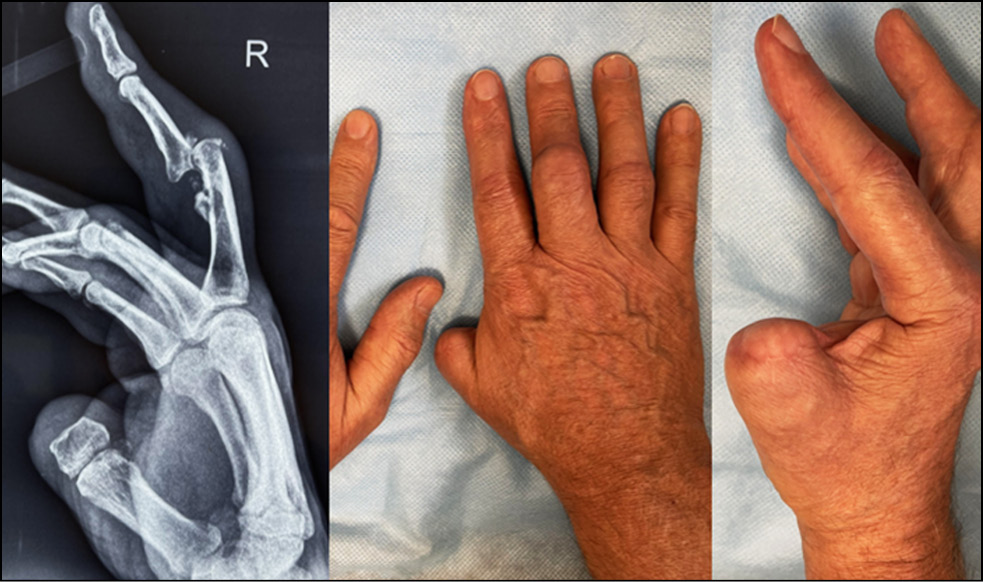

Fig. 1. The appearance of the limb.

Fig. 2. X-ray picture.

Fig. 7. Intraoperative picture after fixation of the graft with screws.

Fig. 8. The result in 2 months after the operation.

Fig. 23. Appearance and function 2 months after the operation.

Thanks to these templates, it was possible to accurately assess the defect of the base of the middle phalanx intraoperatively, resect the malalignment zone, and mark and isolate the bone autograft.

At 6−8 weeks after surgery, all patients had an increase in the amplitude of movements in PIP joints up to 80−95°. The VAS pain syndrome was reduced to 0−1 points. The patients denied pain syndrome in the donor hand area at 6 weeks. Consolidation of the fragment of the palmar edge of the base of the middle phalanx was noted on control radiographs.